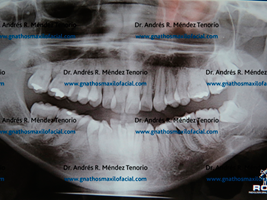

| Radiografía panorámica de un paciente con retención de 3os molares en múltiples posiciones. |